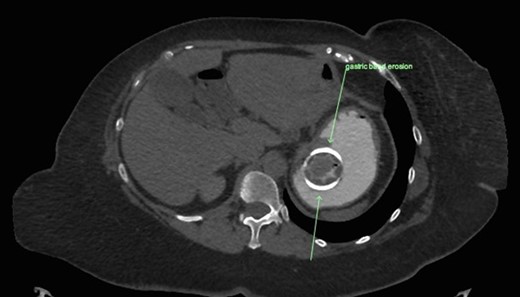

CT abdomen with oral and intravenous contrast was organized to further investigate the tubular foreign body. It revealed concurrent gastric band erosion into gastric lumen and connection tubing eroding into the posterior wall of transverse colon and exiting inferiorly (Figs 2–6). There was no evidence of any oral contrast leak from the stomach.

Sagittal view of CT abdomen showing the gastric band tubing eroding into posterior wall of transverse colon and exiting inferiorly.